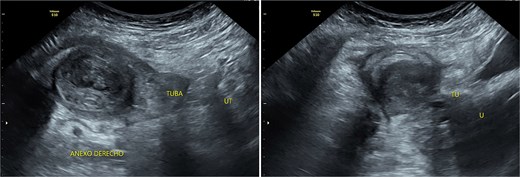

Stage III pelvic inflammatory disease (PID) was suspected based on ultrasound (Figs 1–3) and gynecological examination, which revealed mild bulging of the right lateral fornix, cervical motion tenderness, and a white, non-foul-smelling vaginal discharge. Empiric intravenous antibiotic therapy was initiated, followed by exploratory laparotomy via a Pfannenstiel incision. Intraoperative findings included an 8 × 5 cm uterus, edematous fallopian tubes, and a simple 5 × 5 cm left adnexal cyst. Cystectomy was performed.

Transverse transvaginal ultrasound demonstrating a 4.7 cm bilocular cyst in the left ovary and a dominant follicle in the right ovary, with moderate periovarian fluid adjacent to the right ovary.

Transpelvic ultrasound reveals a heterogeneous mass adjacent to the right adnexa measuring 4.6 × 8.4 cm, predominantly hypoechoic with anechoic areas.

The cervical motion tenderness—a minimum diagnostic criterion—along with fever and elevated CRP, led to a misdiagnosis of PID, with the ultrasound mass interpreted as a tubo-ovarian complex. Retrospectively, both low-normal hemoglobin and absence of mucopurulent cervical discharge were notable. When mucopurulent discharge and leukocytes on vaginal wet prep are absent, PID is unlikely, and alternative diagnoses should be considered [6].

IMTs lack distinctive imaging characteristics. Ultrasound often shows increased vascularity. Contrast-enhanced computed tomography is the imaging modality of choice for gastrointestinal IMTs, which typically present as hypodense, heterogeneous, well-defined masses frequently mistaken for colorectal carcinoma [7].